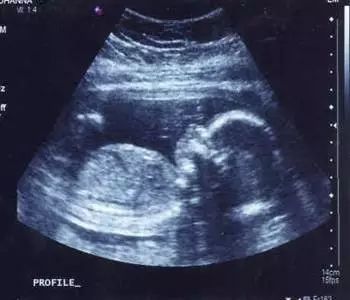

B超维修故障总结